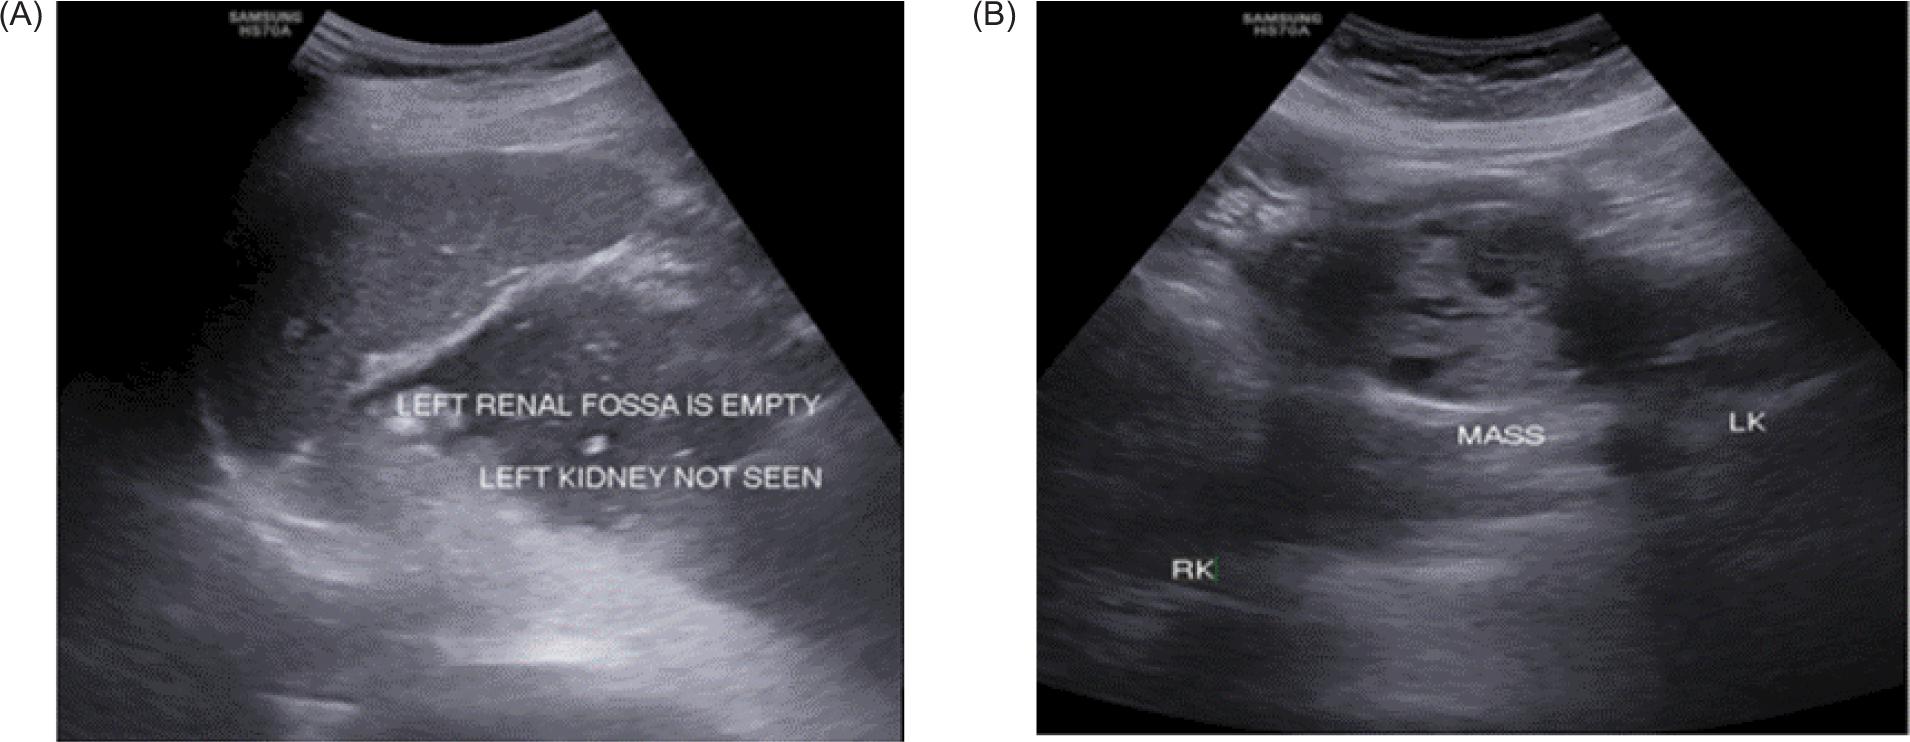

A 43-year-old female patient presented to the Medicine Department complaining of right flank colic that has been persisting for 2 months with a sudden onset and of moderate intensity. The patient also gave history of fever with chills, nausea, and episodes of non-bilious vomiting since 7 days. The patient also complained of burning micturition since 1 month. There was no history of hematuria. No known comorbities were noted. Base-line blood investigations and urine routine examinations were normal. Ultrasound examination of the abdomen revealed HSKs, which were slightly unascended with fusion of both the lower poles of the kidneys by normal renal parenchyma connecting across midline anterior to aorta and inferior vena cava (IVC). A well-defined sold mass of heterogeneous echotexture with few hypoechoic areas within the lesion was seen arising from the upper portion of isthmus (Figure 1).

Figure 1: (A) Left kidney not visualized in the left renal fossa; (B) Well-defined solid mass of heterogeneous echotexture arising from isthmus of HSK.